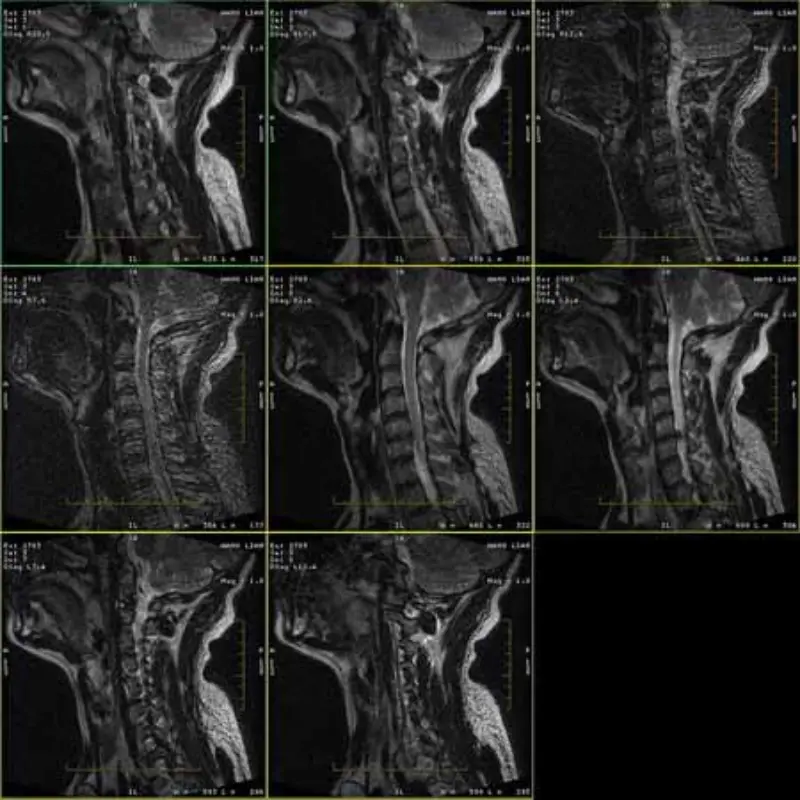

Slike protokolov FRFSE in GRE imajo duha in včasih se v eni seriji pojavijo slike z nizkim SNR. Toda slike protokola SE so normalne.

Poglejte priložite slike.